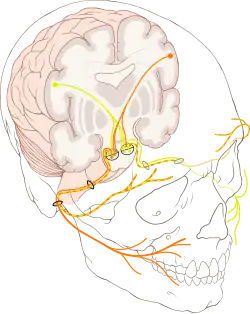

Em laranja: nervos oriundos do hemisfério esquerdo do cérebro

Em amarelo: nervos oriundos do hemisfério direito do cérebro.

Obs.: Observe que a inervação da testa recebe fibras de ambos hemisférios cerebrais (representada em amarelo e laranja).

Os médicos devem determinar se os músculos da testa estão poupados. Devido a uma peculiaridade anatômica, os músculos da testa recebem inervação de ambos os lados do cérebro. A testa pode então ainda estar enrugada (inervada) em um paciente cuja paralisia facial é causada por um problema em um dos hemisférios do cérebro (paralisia facial central). Se o problema reside no próprio nervo facial (paralisia periférica) todos os sinais nervosos são perdidos, incluindo os que vão para a musculatura da testa.